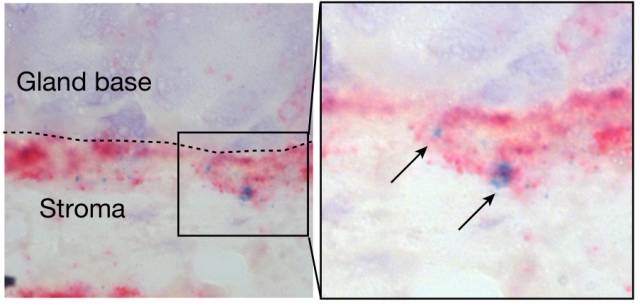

ń╣őňëŹ�´╝î�´╝î�´╝î�´╝îÚęČňůőŠľ»ŠÖ«ŠťŚňůőšÜäńŞ┤ň║ŐňşŽň«ÂMichael Sigalň░▒ňĚ▓š╗ĆňĆĹŠśÄ�´╝î�´╝î�´╝î�´╝îň╣ŻÚŚĘŔ×║ŠŁćŔĆîńŞŹńŻćń╗ůňƬń╝ÜšćĆŠčôŔââš▓śŔćťňĄľŔ▓îšÜäš╗ćŔâ×�´╝î�´╝î�´╝î�´╝îň╣ÂńŞöŔ┐śń╝ÜńżÁňůąňł░Ŕââš▓śŔ杊Ě▒ÚâĘ�´╝î�´╝î�´╝î�´╝îŠŐÁŔżżň╣▓š╗ćŔâ׊▒áŃÇé�ŃÇéŃÇé�ŃÇé�ŃÇéňÉÂ�´╝î�´╝î�´╝î�´╝îSigalŔ┐śŔžćň»čňł░�´╝î�´╝î�´╝î�´╝îŔ┐Öń║Ťň╣▓š╗ćŔâ×Ŕ┐śń╝ÜÚÇÜŔ┐çňó׊Ě╗ňůšá┤šóÄŠŁąň»╣šćĆŠčôňüÜňç║ňĆŹň║ö´╝ł8´╝ëŃÇé�ŃÇéŃÇé�ŃÇé�ŃÇ銜»ńŞŹŠś»Ŕ┐ÖńެňÄćšĘőň»╝Ŕç┤ń║ćŔââšÖî´╝č�´╝č�´╝č�´╝čÚéúŔ»Žš╗抝║ňłÂňĆłŠś»ń╗Çń╣łňĹó´╝č�´╝č�´╝č�´╝č

ň╣▓š╗ćŔâ×ńŻŹń║ÄŔââŔů║šÜäň║ĽÚâĘ�´╝î�´╝î�´╝î�´╝îňĆŚňč║Ŕ┤ĘŠłÉš║Ąš╗┤š╗ćŔâ×ÚçŐŠöżšÜäR-ŔäŐÚźôňŹÁšÖŻňŹÁšÖŻ´╝łš«şňĄ┤´╝ëŔ░âšÉćňó׊«ľŠ┤╗ŠÇž

ňĚ▓ŠťëšáöšęŠë╣Š│Ę�´╝î�´╝î�´╝î�´╝îňťĘŠşúňŞŞň╣▓š╗ćŔâ×ňó׊«ľňÄćšĘőńŞş�´╝î�´╝î�´╝î�´╝îDNAňĄŹňłÂňÄćšĘőńŞşšłćňĆĹšÜäÚÜĆŠť║š¬üňĆśŠś»ńŞÇšžŹň╝║šâłšÜäŔç┤šÖîňŤáš┤á�´╝î�´╝î�´╝î�´╝îňçîÚężÚüŚń╝áń╗ąňĆŐŠâůňŻóňŤáš┤ášşë´╝ł9´╝ëŃÇé�ŃÇéŃÇé�ŃÇé�ŃÇéňŤáŠşĄ�´╝î�´╝î�´╝î�´╝îň╣ŻÚŚĘŔ×║ŠŁćŔĆîňżłŠťëňĆ»Ŕ⯊ś»ÚÇÜŔ┐çňó×Ŕ┐ŤŔââš▓śŔćťň╣▓š╗ćŔâךÜäňĄ¬Ŕ┐çňó׊«ľ�´╝î�´╝î�´╝î�´╝îň╝ĽŔÁĚňĄžň«ŚDNAŠŹčń╝Ą�´╝î�´╝î�´╝î�´╝ǚ╗łŔ»▒ň»╝ŔââšÖîšÜäšłćňĆĹŃÇé�ŃÇéŃÇé�ŃÇé�ŃÇé

ńŞ║ń║ćší«ň«Üň╣ŻÚŚĘŔ×║ŠŁćŔĆîŔ»Žš╗抜»ŠÇÄŠáĚňó×Ŕ┐ŤŔââš▓śŔćťň╣▓š╗ćŔâ×ňó׊«ľšÜäŃÇé�ŃÇéŃÇé�ŃÇé�ŃÇéMeyerňŹÜňúźŠÄąš║│ňŹĽňłćňşÉňÄčńŻŹŠŁéń║ĄŠëőŔë║ň»╣ň░ĆÚ╝áŔââš▓śŔćťň╣▓š╗ćŔâ×ńŞżŔíîš│╗š╗čň뾊×ÉŃÇé�ŃÇéŃÇé�ŃÇé�ŃÇ銼łŠ×ťňĆĹŠśÄ�´╝î�´╝î�´╝î�´╝îň░ĆÚ╝ášÜäŔââš▓śŔćťńŞő�´╝î�´╝î�´╝î�´╝îńŻŹń║ÄŔââŔů║ňč║ň║ĽšÜäň╣▓š╗ćŔâ׊▒áńŞşń┐ŁňşśńŞĄšžŹňĚ«ňłźš▒╗ň×őšÜäň╣▓š╗ćŔâ×ŃÇé�ŃÇéŃÇé�ŃÇé�ŃÇéńŞÇšžŹň╣▓š╗ćŔâ×ňłćŔžúŠ░┤ň╣│ńŻÄ�´╝î�´╝î�´╝î�´╝îňó׊«ľŔâŻňŐŤň╝║�´╝î�´╝î�´╝î�´╝îňĆŽńŞÇšžŹňłćŔžúŠ░┤ň╣│ŔżâÚźś�´╝î�´╝î�´╝î�´╝îňó׊«ľŔâŻňŐŤŔżâň╝▒ŃÇé�ŃÇéŃÇé�ŃÇé�ŃÇé

ňÉÂ�´╝î�´╝î�´╝î�´╝îMeyerňŹÜňúźŔ┐śňĆĹŠśÄ�´╝î�´╝î�´╝î�´╝îňŻôň╣ŻÚŚĘŔ×║ŠŁćŔĆîńżÁňůąŠŚÂ�´╝î�´╝î�´╝î�´╝îŔââš▓śŔćťńŞőŠľ╣šÜäÚŚ┤Ŕ┤ĘŠłÉš║Ąš╗┤š╗ćŔâ×ń╝ÜŠŞŚÚÇĆńŞÇšžŹňÉŹńŞ║R-ŔäŐÚźôňŹÁšÖŻ´╝łRspo´╝ëšÜäšëęŔ┤Ę�´╝î�´╝î�´╝î�´╝îńŻťšöĘń║ÄŔââš▓śŔćťńŞőŠľ╣ň╣▓š╗ćŔâ׊▒á�´╝î�´╝î�´╝î�´╝îŠ┐ÇŠ┤╗ň╣▓š╗ćŔâךÜäWNTÚÇÜŔĚ»Ŕ░âšÉćň╣▓š╗ćŔâךÜäňó׊«ľń╗ąň║öň»╣ň╣ŻÚŚĘŔ×║ŠŁćŔĆîšćĆŠčôŃÇé�ŃÇéŃÇé�ŃÇé�ŃÇé